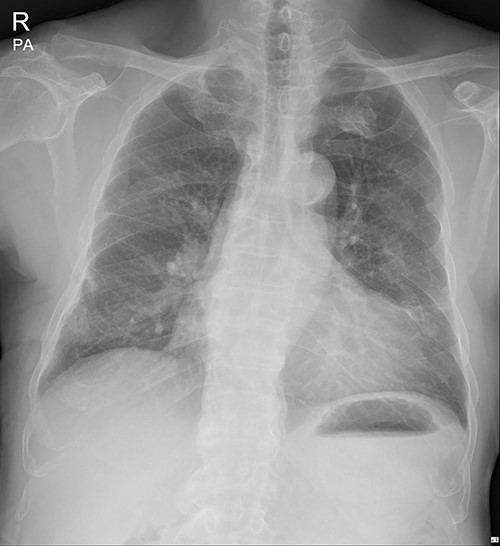

On 25 November 2021, a 68-year-old male, a victim of a motor vehicle accident, presented with multiple rib fractures and hemopneumothorax in the right hemithorax. On hospital Day 2, oxygen saturation gradually dropped under 90% despite proper support, and the patient’s right chest wall showed a newly occurred flail motion. We decided to stabilize rib fractures emergently. The operation was performed routinely, with bicortical screw fixation after exploration of the thoracic cavity. There were no specific intraoperative or postoperative events, and the patient was safely discharged from the hospital with stitches removed on hospital Day 17 (Fig. 1.).

Immediate postoperative chest X-ray after plates removal (24 February 2022).